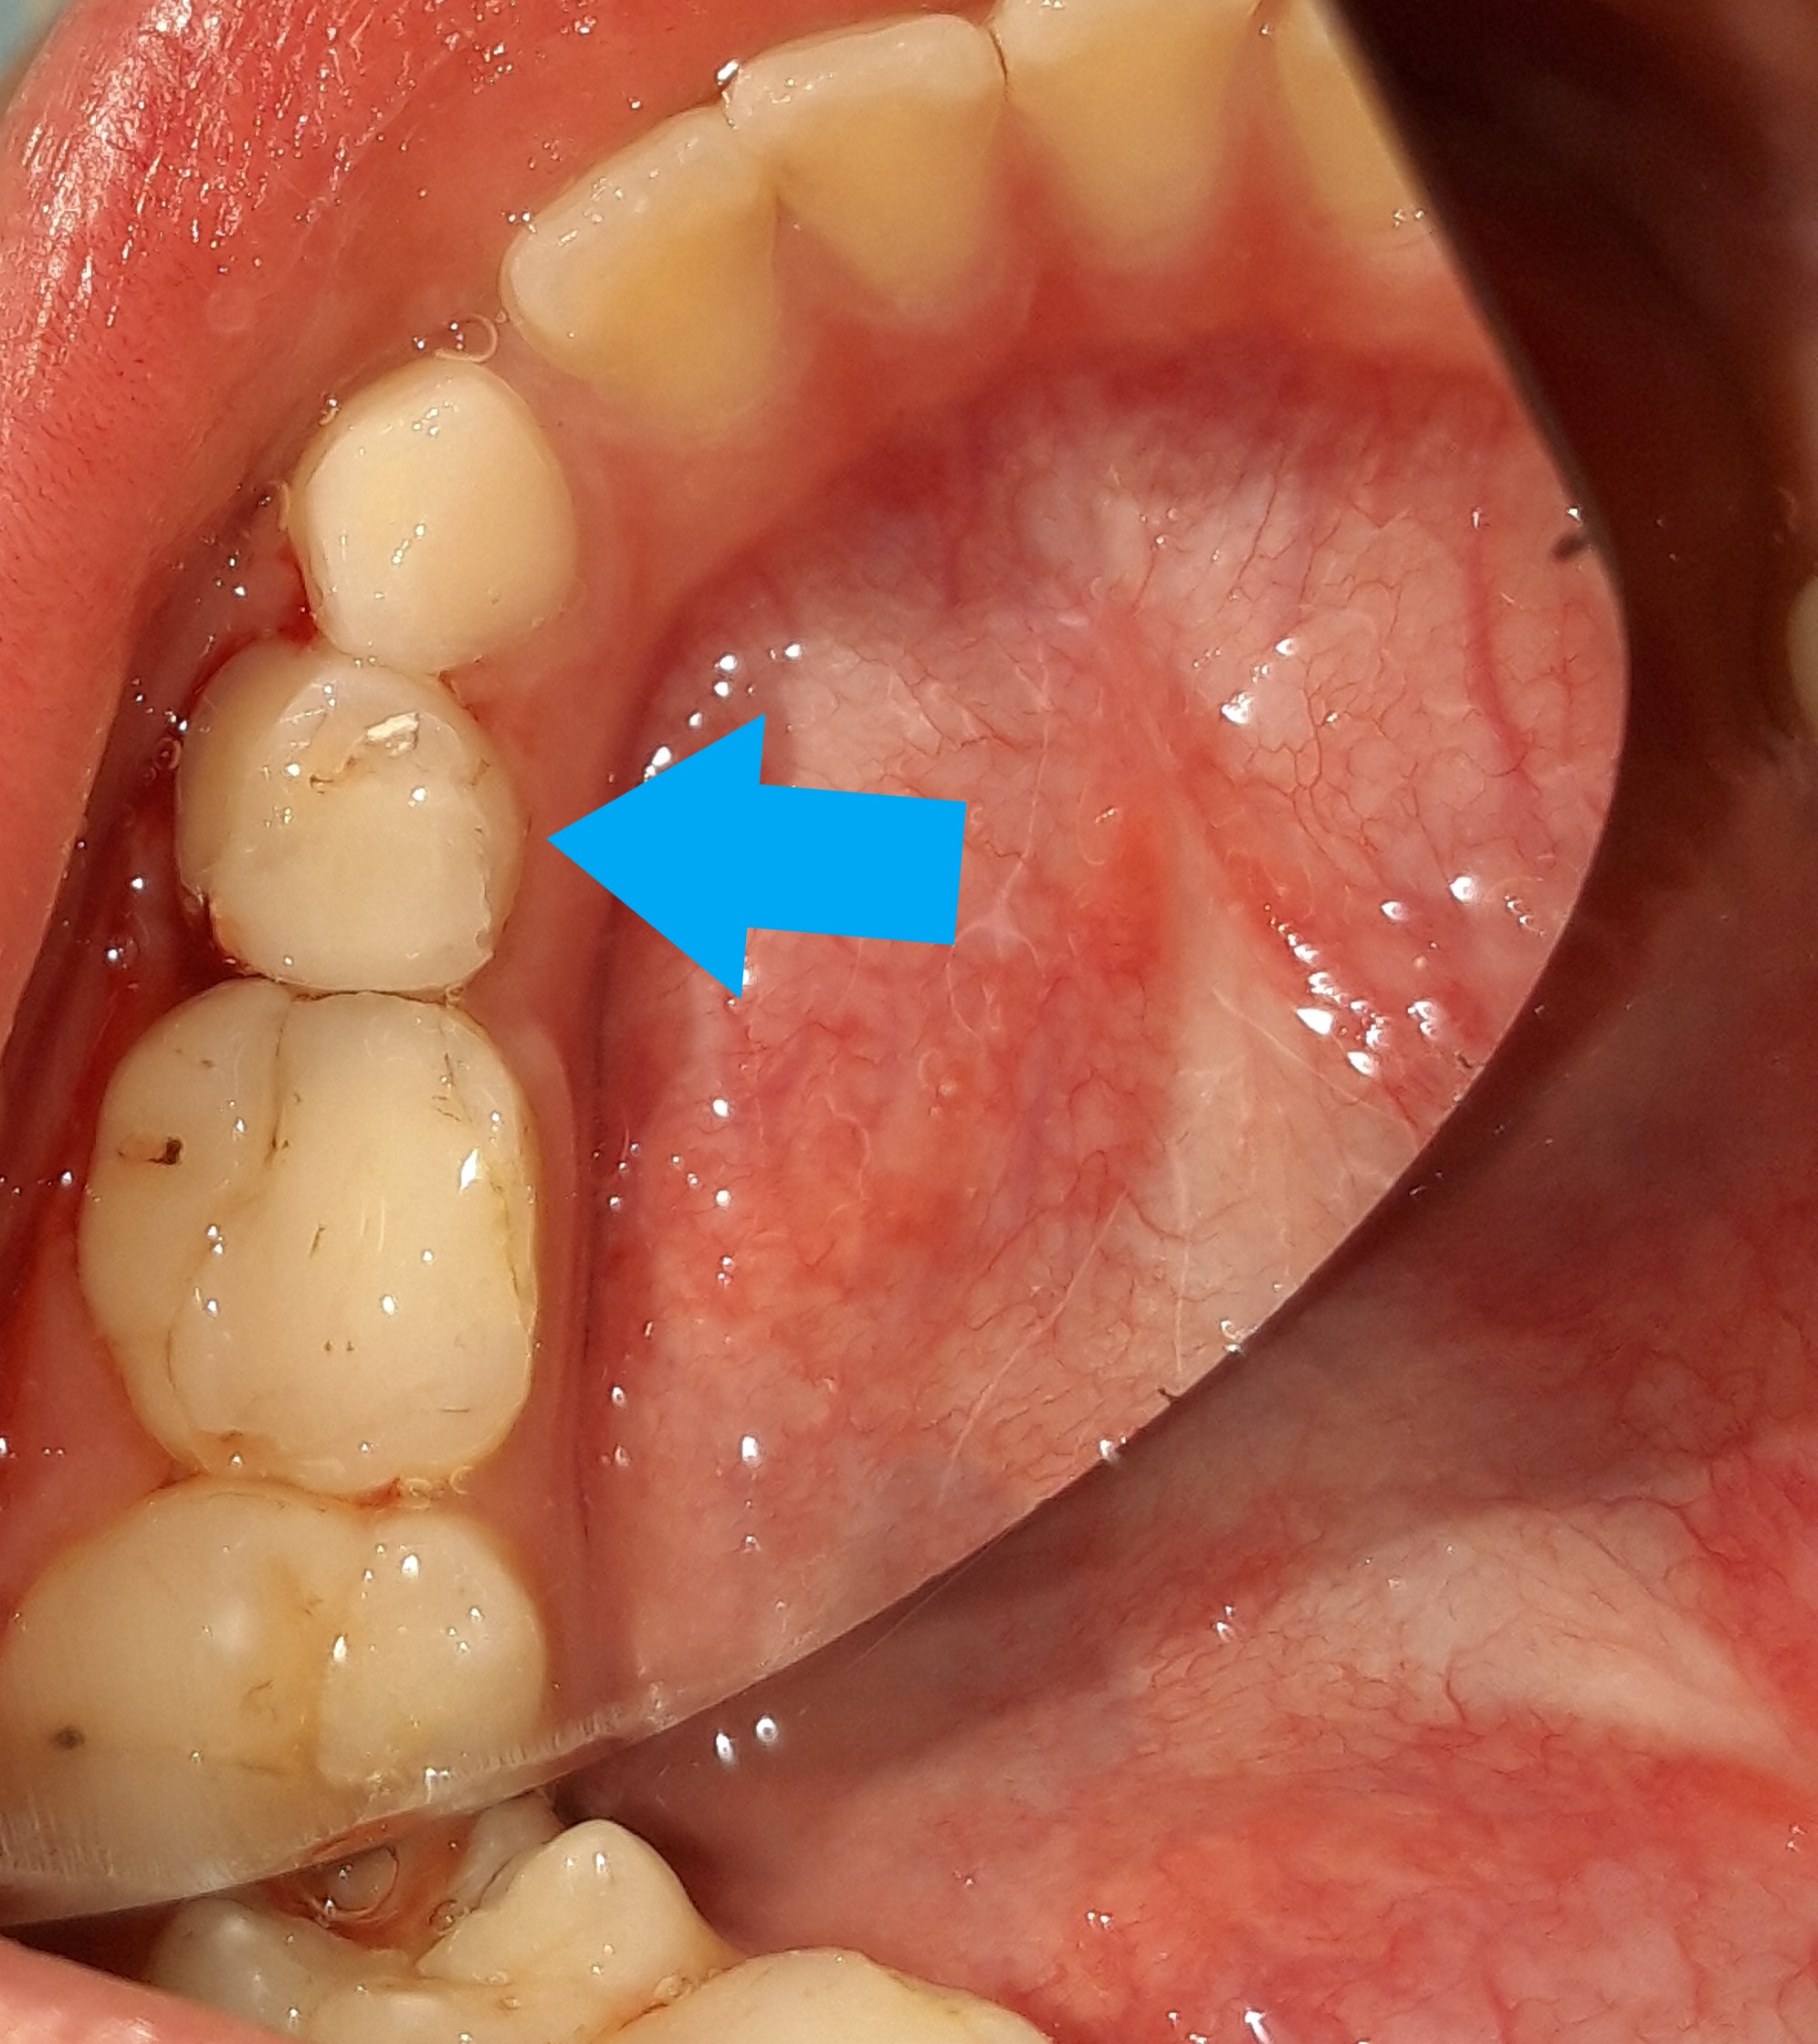

Η μικρή δεσποινίς προσήλθε στο ιατρείο για την αποκατάσταση της μικρής τρυπούλας στο νεογιλό γομφίο της κάτω γνάθου. Εφόσον το οδοντικό έλλειμμα ήταν μικρό η διαδικασία του σφραγίσματος πραγματοποιήθηκε χωρίς την χορήγηση τοπικού αναισθητικού.

ΠΡΙΝ

ΜΕΤΑ